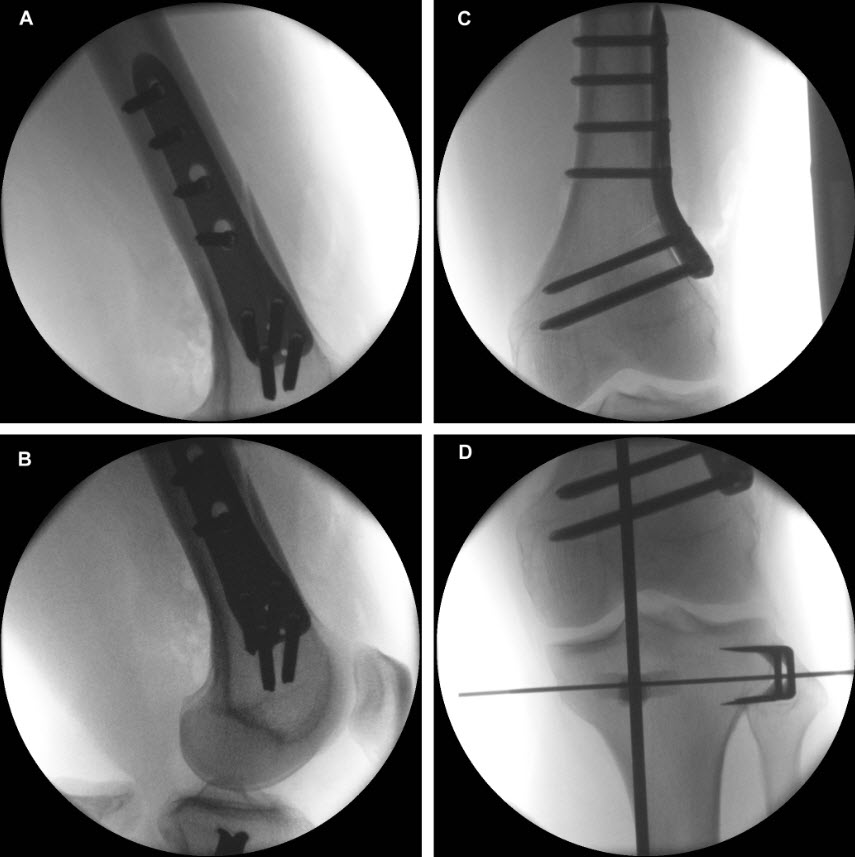

Following completion of the DFO and fixation with the TomoFix MDF Anatomical (Fig 10) the new aiming arm and K-wire guide system was used for the open wedge HTO.

After performing a minimally invasive approach at the medial proximal tibia, the first step of the new K-wire guiding system is definition of the hinge point with a K-wire from the lateral aspect (Fig 11). The guiding arm for the osteotomy was then inserted with the radiolucent hook in situ (Fig 12). The guiding arm should be adjusted under intensifier control and finally fixed with a K-wire. At this stage two K-wires for the osteotomy can be inserted and the guiding arm can be removed. The saw guide is then mounted and guides the sawblade safely (Fig 13 and 14).